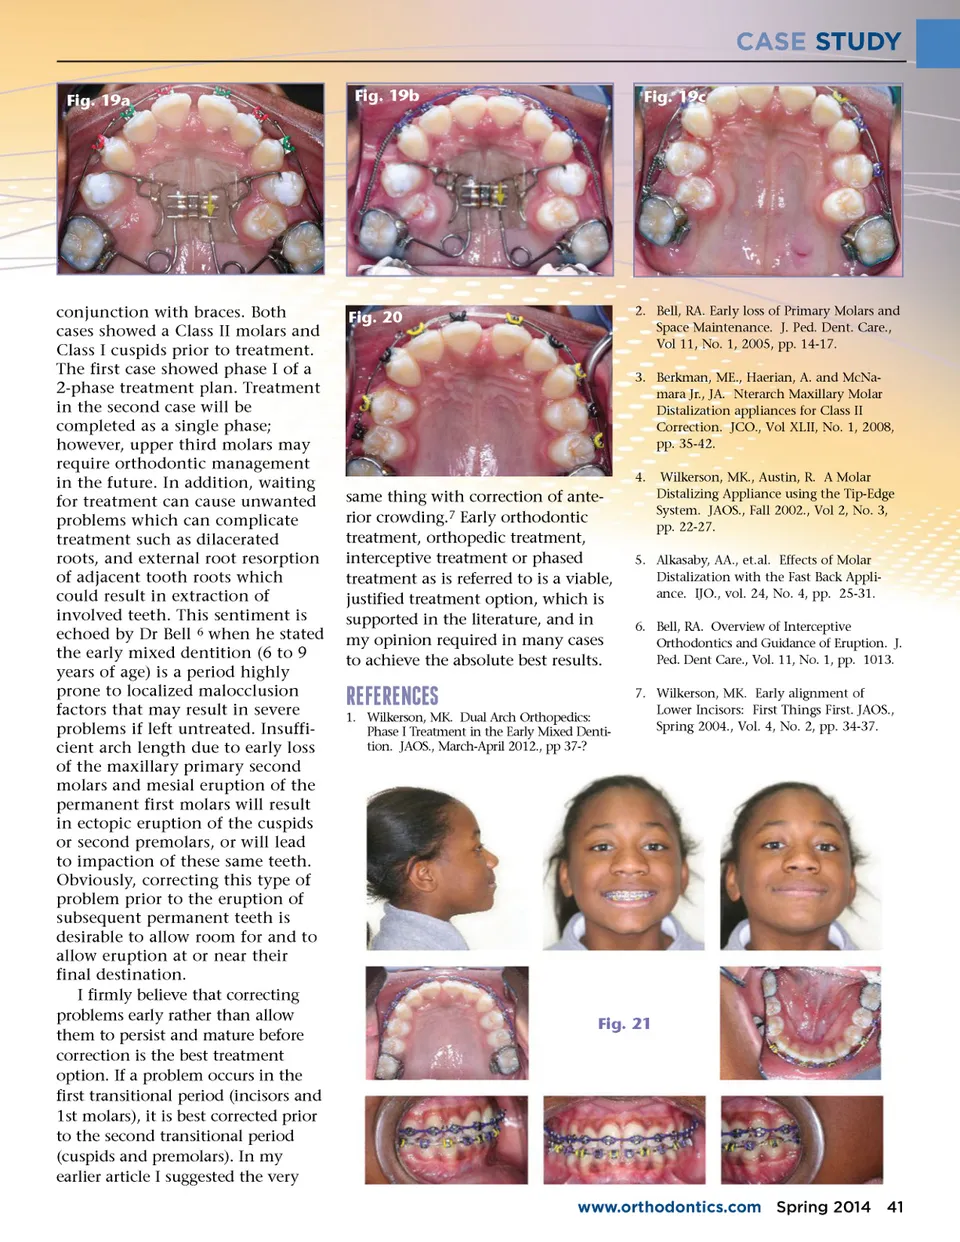

CASE STUDY �c;! b;e;! b;  !f;d;f; c;e;e; f;b;! e;c; a; d;e;!e;d;f; e;!f;d;!d;c; f; !f;c;! e;a;b;a;f;!d;�f; d;f;�e;e; ! c;e; c;e;e; f;b;c;!b;a;!f; ! a;f; f;e; d;f; f;!c; f;b;c;  lower arch and a 10mm discrepancy in the upper arch. Even so, treat-ment was delayed. A year and a half later, routine bitewing x-rays (Fig. 16), and another panoramic x-ray (Fig. 17) reveal the extent of the mesial drift of the maxillary first permanent molar which can be seen nearly touching the distal of the maxillary permanent first premolars. Treatment did not commence until the upper left second premolar was noted to be erupting in the palate. At this stage there were no primary teeth remaining so treatment was planned for a single phase. The main objective was to distalize the upper permanent first molars to allow room for the second premolars. JP was referred to the oral surgeon for extraction of permanent second molars, as well as a upper labial frenectomy. Third molars were present, and removal of the seconds would hasten distalization of the first molars. On October 31, 2012 a T-Rex was cemented (Fig. 18) and orthodontic treatment began as a combination of orthopedics followed by comprehensive orthodontics. Treatment was started in the upper arch only. The T-Rex appliance was removed after 4 ½ months. Figs.19a-c shows treatment progression until the T-Rex was removed. The second premolars were in correct position in the dental arch after 8 months. (Fig. 20) JP has reached Stage 3, and her orthodontic treatment is near completion. (Fig. 21) Her total treat-ment time is estimated to be around 18 months. These two case reports show correction of mesial displaced upper permanent first molars using a T-Rex appliance in Fig. 15 Fig. 16 molar relationship was class II due to mesial drift after ectopic eruption and early loss of the primary second molars. Her skeletal pattern was class I, with a natural ethnic bimaxillary protrusion. A mixed dentition analy-sis revealed no crowding in the Fig. 18 Fig. 17 40 Spring 2014 JAOS